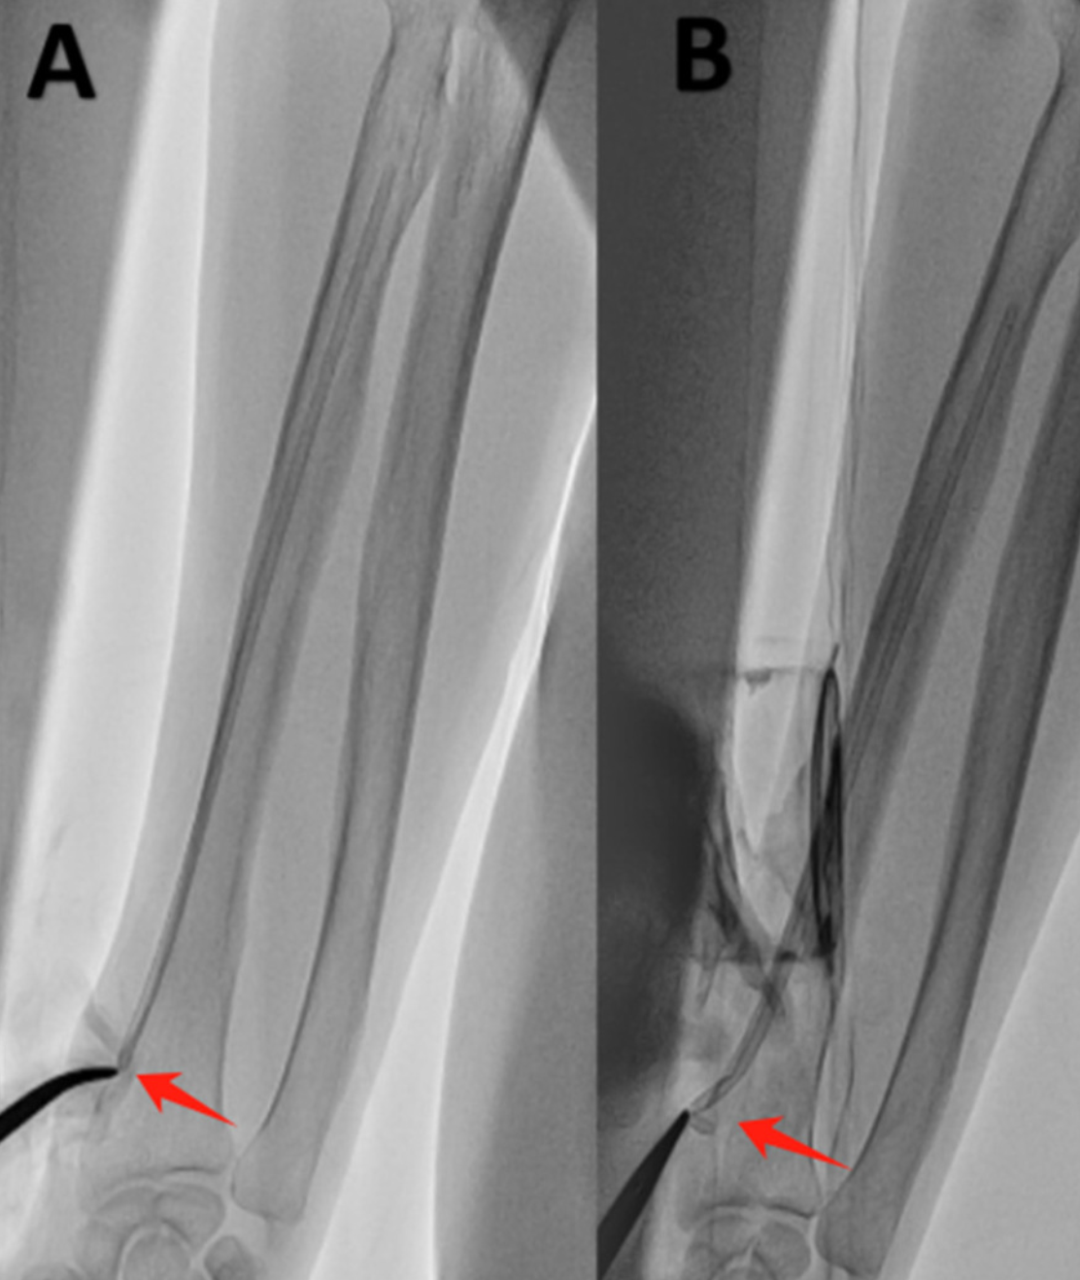

移除桡动脉鞘管时发现鞘管远心端断裂,鞘管残端完全滞留于右桡动脉内:

2. 透视观察鞘管残端(鞘管残端恰位于穿刺口下方)

(A)鞘管残端的位置 (B)止血钳夹取残端 (C)取出后的断裂鞘管